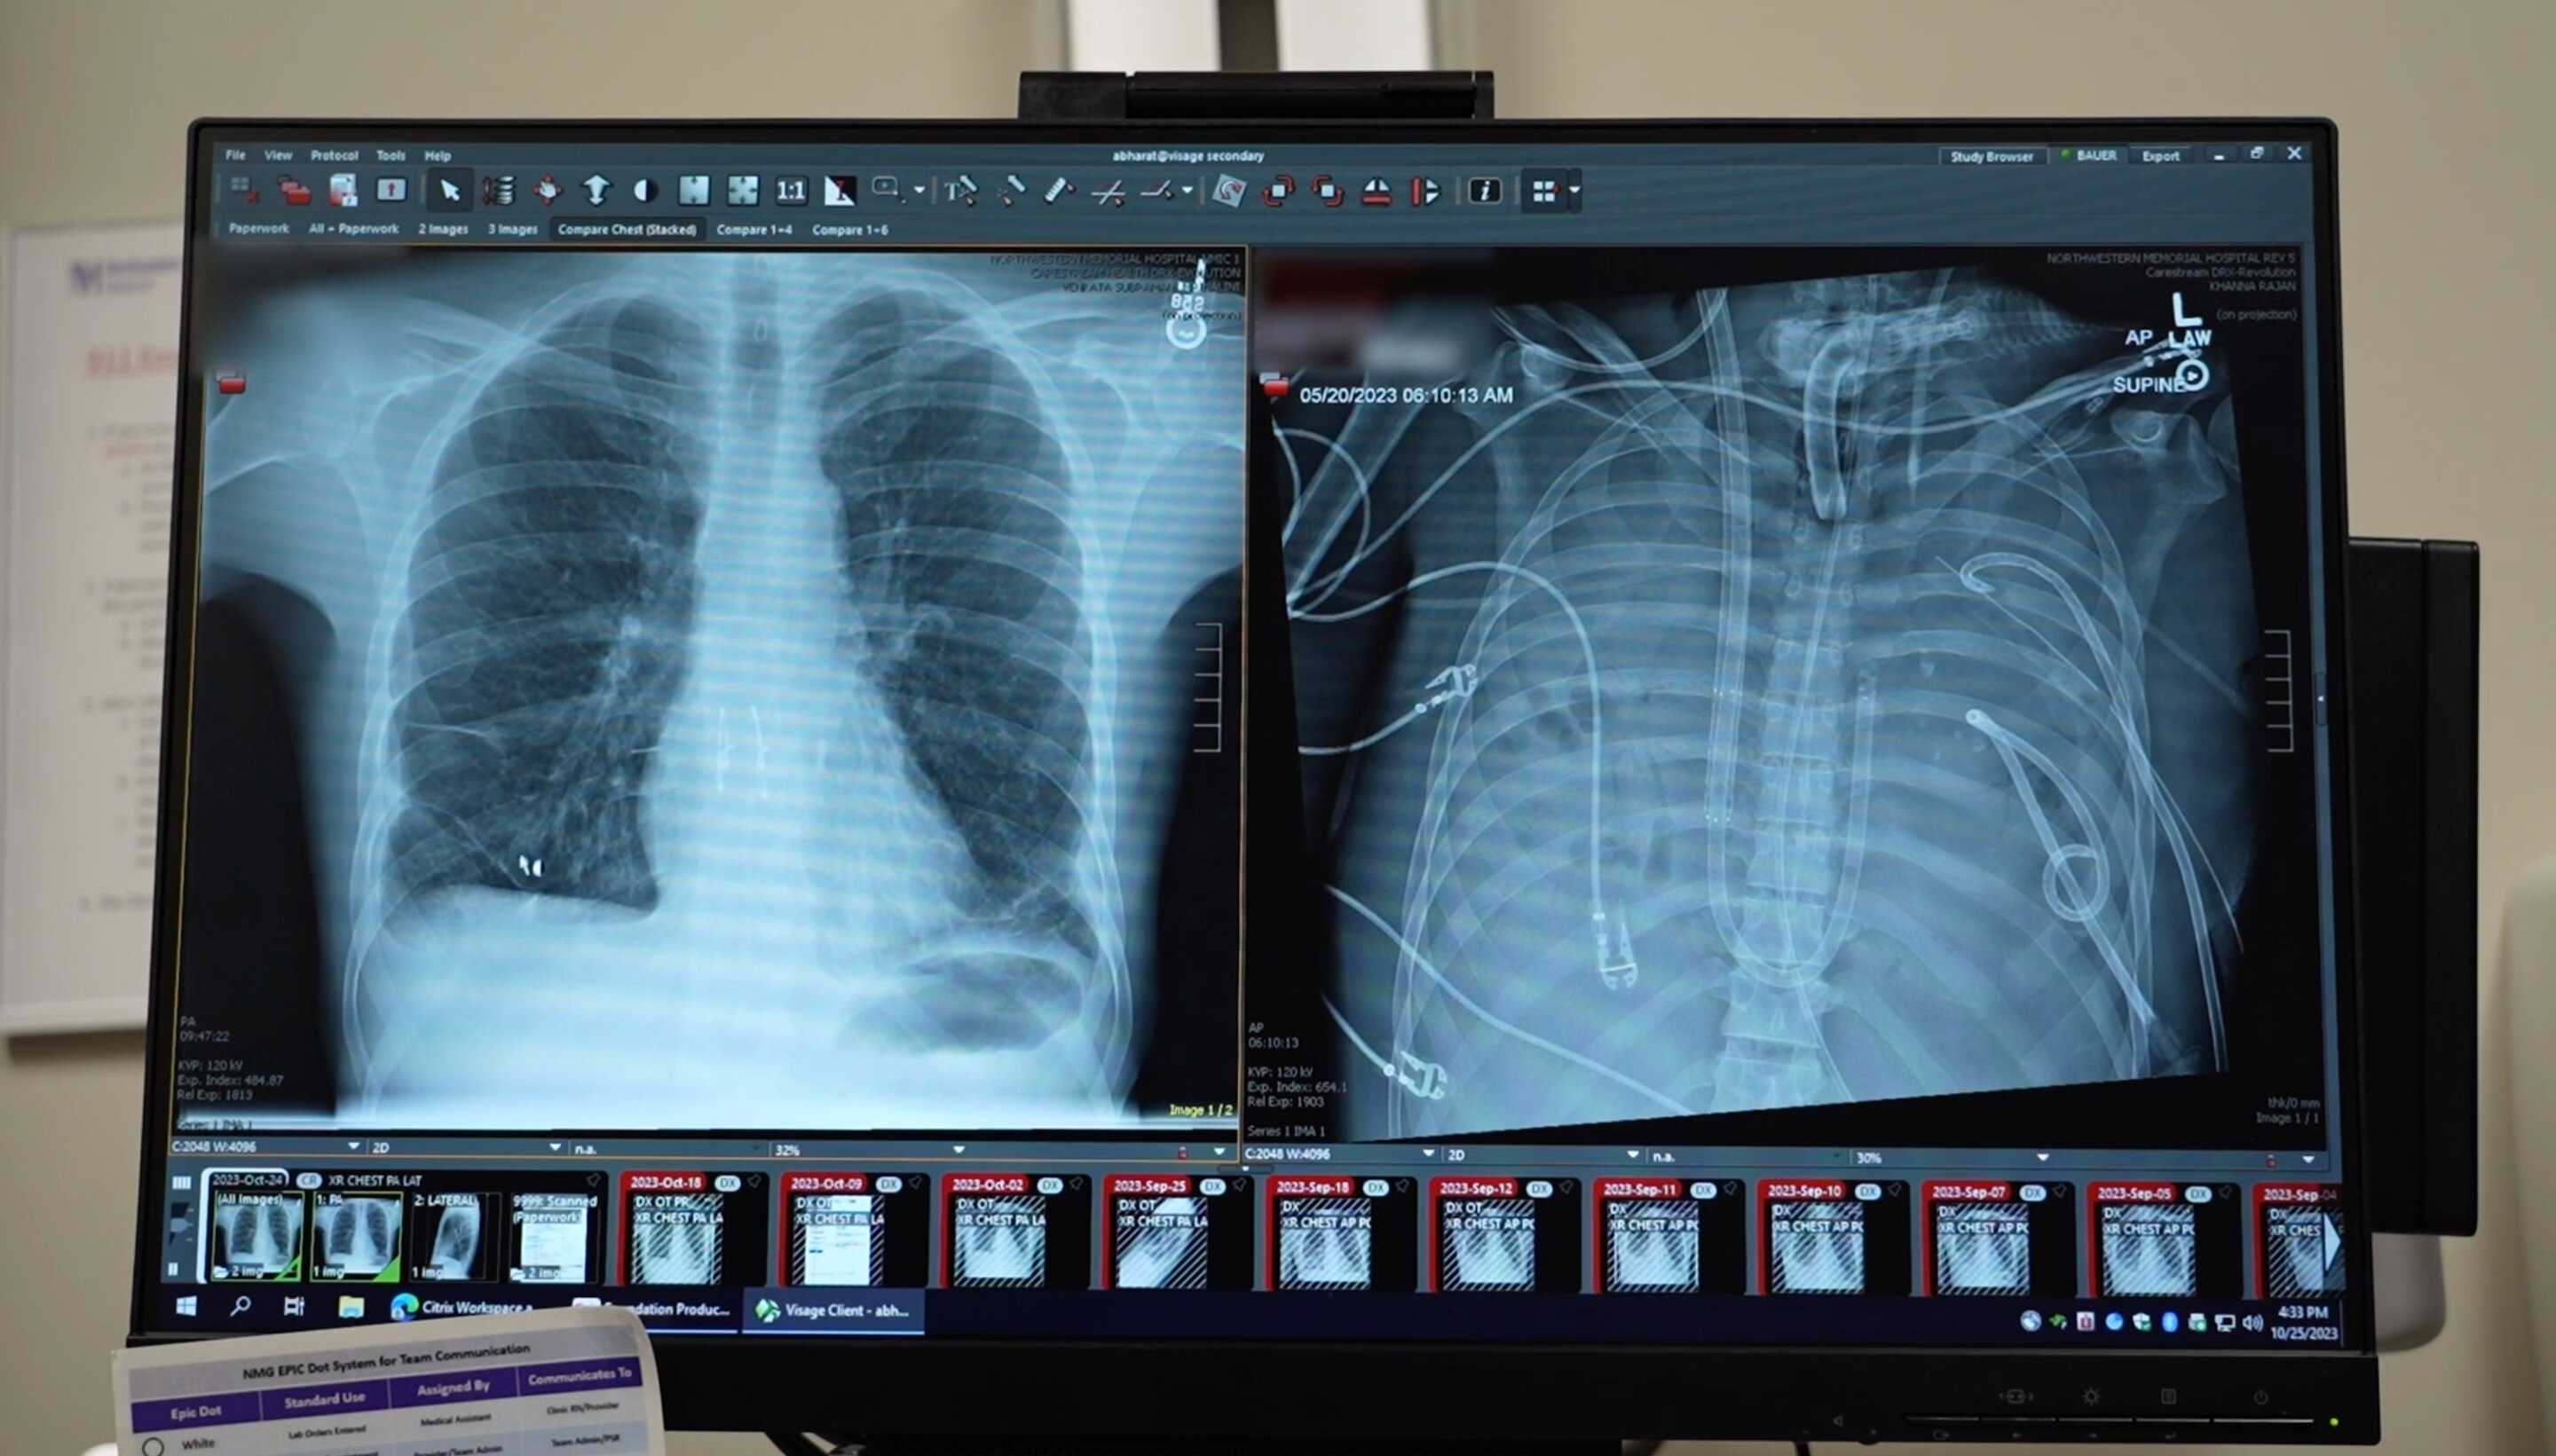

Через 48 часов нахождения на искусственном легком пациенту выполнили двустороннюю трансплантацию донорских легких по стандартной технологии. Вирус гриппа В и синегнойная палочка у него определялись во время операции, но не после нее. Через три дня пациента отключили от ЭКМО, через неделю — от искусственной вентиляции и через восемь недель выписали из стационара. Чрезбронхиальные биопсии через 3, 6, 9 и 12 месяцев не выявили признаков острого отторжения, через 24 месяца трансплантат функционировал полноценно, функция внешнего дыхания была удовлетворительной, уплотнений и выпота на рентгенограмме грудной клетки не было. Патологоанатомическое исследование удаленных легких выявило обширный некроз и фиброз с диффузной инфильтрацией иммунными клетками и отложениями коллагена. Секвенирование РНК одиночных клеток и пространственный транскриптомный анализ подтвердили необратимые диффузные повреждения легких с тяжелым фиброзом.